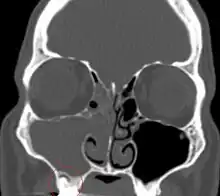

Diagnosis

The diagnosis of odontogenic sinusitis is often challenging and requires a multidisciplinary approach involving otolaryngologists and dental specialists. Clinical examination and patient history play a crucial role.[11] Radiological investigation, including dental panoramic radiographs, computed tomography scans, and cone-beam computed tomography can help visualize the relationship between the maxillary sinuses and the dental structures, identify dental pathologies, and assess the extent of sinus involvement.[1]